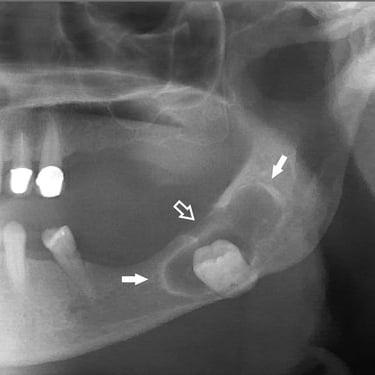

Quiste dentígero

Un quiste dentígero es un saco lleno de líquido que se forma alrededor de la corona de un diente no erupcionado.

Los pacientes pueden notar una hinchazón indolora en la mandíbula.

El tratamiento incluye la extirpación quirúrgica del quiste y, a veces, la extracción del diente involucrado.